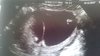

To jest zdjęcie po ktorym lekarz stwierdził, ze bliznieta sa dwujajowe. Zrobione w 13 tygodniu. Na dole widać te rozchodzaca sie powloke- taki trojkacik.

Załączniki

• DSC_0391.JPG

DSC_0391.JPG

1,4 MB · Wyświetleń: 138

Widze, rozumiem musze zobaczyc na moje nagranie czy tam czegos takiego nie widac, chociaż oglądałam wiele razy i nie przypominam sobie, ale jak sie nie wie na co patrzec to sie nie zwraca uwagi ;)